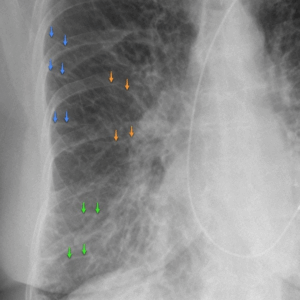

胸部レントゲンとCTの違い

胸部レントゲンは、少ない放射線量で肺全体を広く見渡すスクリーニング的な検査です。一方でCTは、より精細な断面画像が得られるため、索条影・線状影の位置や原因を詳しく調べるときに有用です。

レントゲンで異常が示唆された場合、必要に応じてCTで精密検査を行うケースもあります。

画像検査(CT・MRI)

CTでは肺を細かい断面で評価できるため、影の形状や広がりをより詳しく把握できます。MRIは心臓や大血管の状態も含めて確認したい場合などに併用することがあります。

画像情報を総合しながら、呼吸器専門医が病変の有無や進行度を見極めていきます。